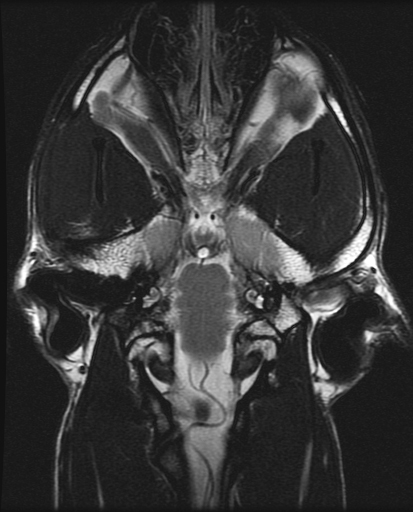

IRM de la base du cerveau en plan dorsal.

Le chien de Charlie est entre les canthus médiaux de la libéllule et il halète!